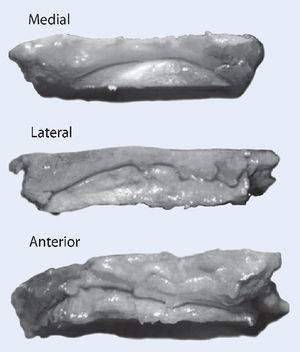

La técnica quirúrgica se ilustra en las figs. 1-13.

Fig. 5 Decortización de la cara medial del peroné distal con sierra oscilante. Esto aumenta la potencia biológica de la refijación.